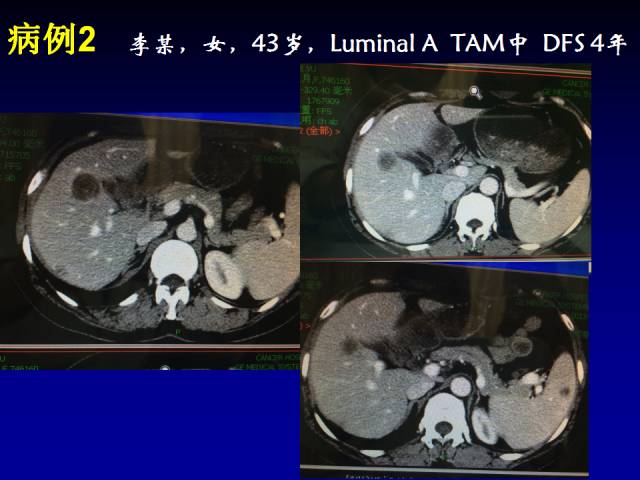

病例2 :一位43岁Luminal A型患者,在辅助TAM治疗过程中发现了多发肝转移,患者在试验入组后接受OFS+依西美坦治疗。在治疗过程中,患者的转移病灶持续缓解,缓解时间8个月(如下图)。